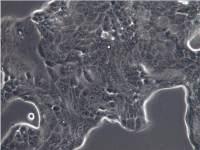

细胞名称:NK-92MI 人恶性非霍奇金淋巴瘤患者的自然杀伤细胞

形 态:悬浮